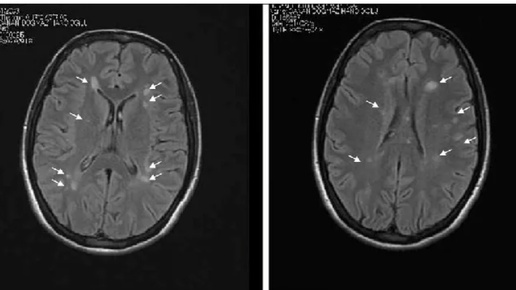

Болезнь Бинсвангера на примере клинического случая

Болезнь Бинсвангера (субкортикальная артериосклеротическая дисциркуляторная энцефалопатия, также известная как «малая» сосудистая деменция) – прогрессирующее заболевание, характеризующееся утолщением и снижением активности мышечного слоя артерий на фоне длительно существующей артериальной гипертензии, вследствие чего нарушается кровоснабжение исключительно белого вещества головного мозга. Вследствие ишемии происходит постепенное уменьшение объёма белого вещества головного мозга с развитием диффузной церебральной атрофии и компенсаторным расширением желудочковой системы...